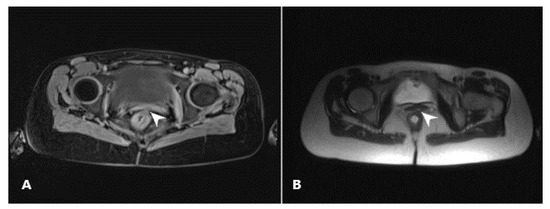

2.2. Diagnostic Assessment